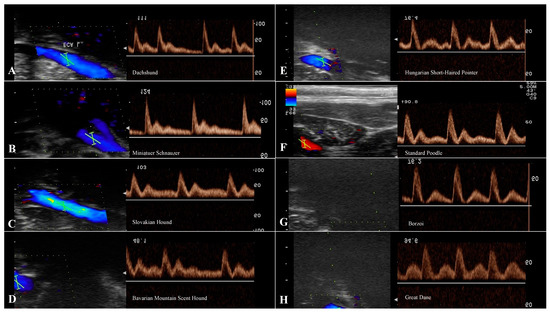

3.5. Evaluation of the ICA

| ICA | ||||||

|---|---|---|---|---|---|---|

| n | RI | PSV (cm/s) | EDV (cm/s) | S/D | ||

| Small breeds | Dachshund | 13 | 0.56 | 29.52 ± 8.86 | 12.82 ± 4.52 | 2.40 ± 0.47 |

| Miniature Schnauzer | 13 | 0.60 | 32.75 ± 8.47 | 12.29 ± 1.99 | 2.66 ± 0.44 | |

| Medium breeds | Slovakian Hound | 13 | 0.60 | 28.55 ± 7.87 | 11.51 ± 3.43 | 2.56 ± 0.33 |

| Bavarian Mountain Scent Hound | 13 | 0.58 | 31.99 ±16.22 | 11.54 ± 2.61 | 2.7 ± 0.74 | |

| Large breeds | Hungarian Short-Haired Pointer | 13 | 0.66 | 24.55 ± 7.19 | 8.84 ± 3.58 | 2.98 ± 0.49 |

| Standard Poodle | 13 | 0.64 | 24.42 ± 7.71 | 9.31 ± 3.43 | 2.73 ± 0.25 | |

| Giant breeds | Borzoi | 13 | 0.64 | 43.26 ± 12.3 | 17.2 ± 3.18 | 2.55 ± 0.36 |

| Great Dane | 13 | 0.66 | 29.27 ± 8.8 | 10.17 ± 4.08 | 3.01 ± 0.48 | |